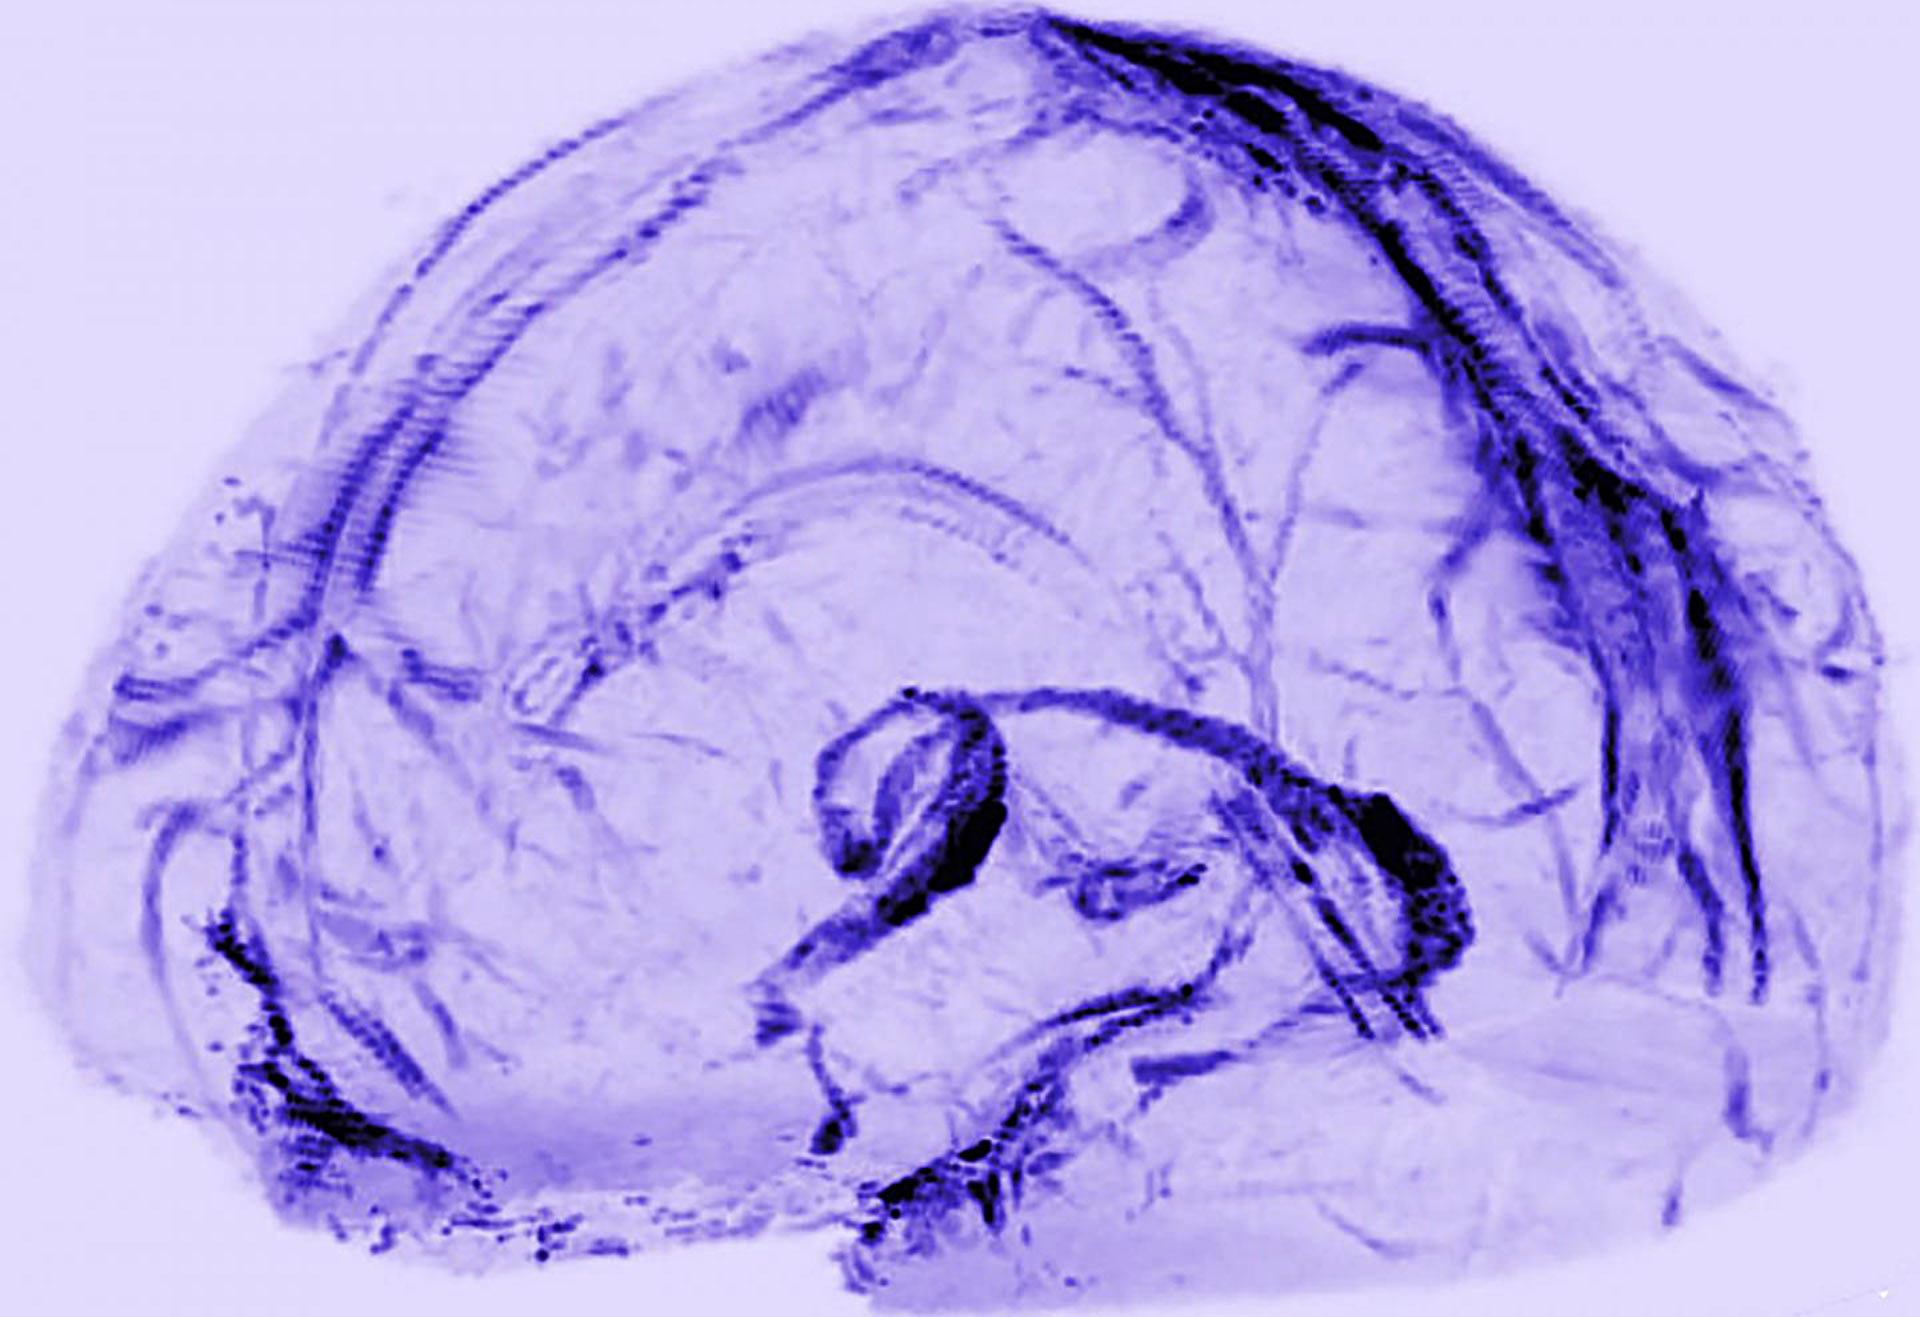

Brain scans of healthy volunteers showed that human brains may drain waste through lymphatic vessels. Image credit: Reich Lab, NIH / NINDS.

To look for the vessels, Dr. Reich and co-authors used MRI to scan the brains of five healthy volunteers who had been injected with gadobutrol, a magnetic dye typically used to visualize brain blood vessels damaged by diseases, such as multiple sclerosis or cancer.

At first, when the researchers set the MRI to see blood vessels, the dura lit up brightly, and they could not see any signs of the lymphatic system.

But, when they tuned the scanner differently, the blood vessels disappeared, and the scientists saw that dura also contained smaller but almost equally bright spots and lines which they suspected were lymph vessels.

They also found evidence for blood and lymph vessels in the dura of autopsied human brain tissue.